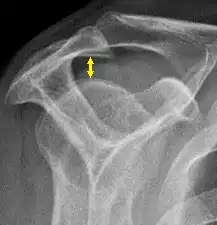

- The normal glenohumeral space is 4–5 mm.[1]

- The normal subacromial space in shoulder radiographs is 9–10 mm; this space is significantly greater in men, with a slight reduction with age.[2] In middle age, a subacromial space less than 6 mm is pathological, and may indicate a rupture of the tendon of the supraspinatus muscle.[2]